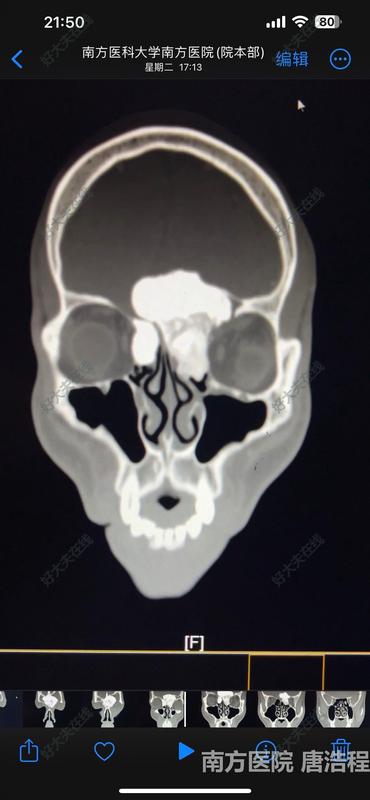

患者因“头痛伴有鼻部、眼部畸形”就诊,行鼻窦CT检查发现鼻窦前颅底眼眶巨大骨瘤,肿瘤占据双侧额窦、筛窦,突入颅内和左侧眼眶